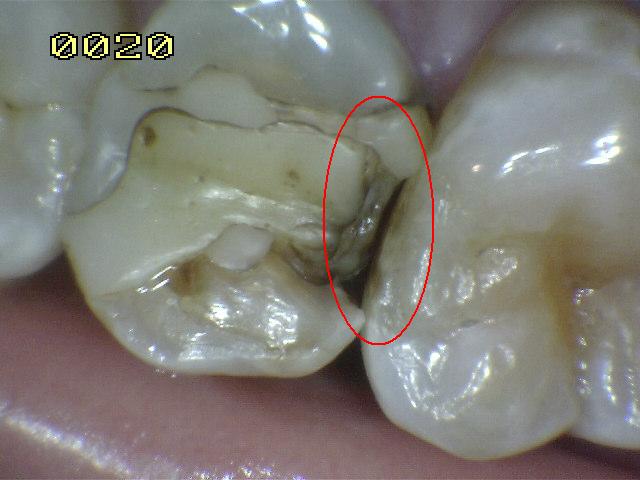

Código 4

(Caries Moderada): Sombra oscura

de dentina subyacente al esmalte intacto con o sin interrupción

localizada del esmalte

- La superficie de los dientes

puede tener características de código 2 y tiene una

sombra de dentina con cambio de color que es visible a

través de una superficie de esmalte aparentemente

intacto o con ruptura localizada en el esmalte pero sin

dentina visible. Este aspecto se ve más fácilmente

cuando el diente está húmedo y es una sombra oscura e

intrínseca que puede ser de color gris, azul, naranja o

café.

- Nota: observar el diente húmedo y luego seco. Esta

lesión debe distinguirse de sombras ocasionadas por

amalgama.